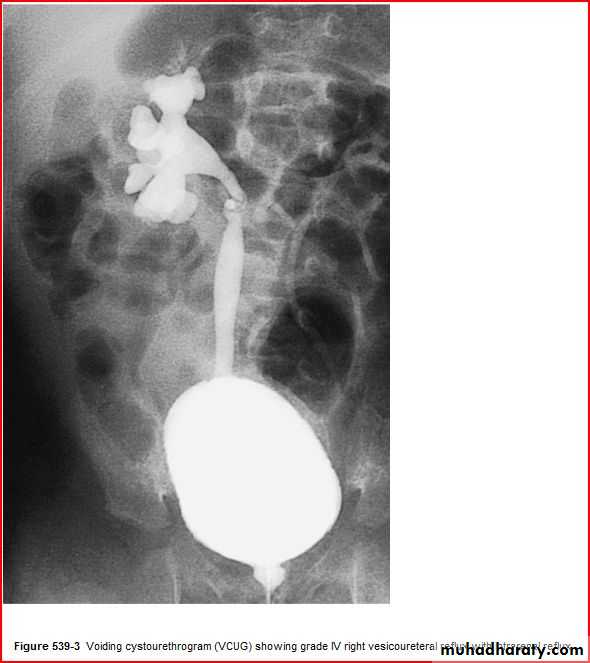

Current jelly stool intussuception

( coil spring sign )Coil spring sign intussusseption

3 signs >> current jelly stool

Suscage mass

Prolapse of the mass theough rectum